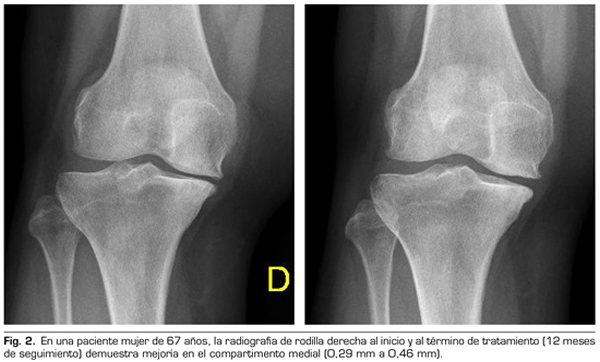

Variables radiológicas: en 53 pacientes analizados radiológicamente (según protocolo estandarizado) al año de seguimiento después del tratamiento con ozono, el compartimento interno aumento significativamente de 4.12 ± 1.41 mm a 4.4 ± 1.35 mm (p = 0.0008) y el compartimento externo aumentó de 6 ± 1.37 a 6.16 ± 1.4 mm (p = 0.0753).

Figura 2